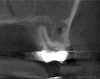

(6.) Preoperative CBCT image showing periapical pathosis of tooth No. 2 in communication with the sinus.

Figure 6

(7.) Postoperative CBCT images taken 3 months after NSRCT (ie, 6 weeks after sinus surgery), showing sinus clearing and reduction in the size of the PAO lesion.

Figure 7

(8.) Postoperative CBCT images taken 3 months after NSRCT (ie, 6 weeks after sinus surgery), showing sinus clearing and reduction in the size of the PAO lesion.

Figure 8

A 58-year-old female patient presented to the office with a 3-month history of acute sinusitis, during which six courses of antibiotics, including penicillin, cephalosporin, and quinolone drugs, had failed to resolve her symptoms. She had been referred for endodontic evaluation by her ENT specialist after imaging revealed endodontic pathosis of tooth No. 2. On initial presentation, tooth No. 2 was nonvital (ie, nonresponsive to cold or electric pulp testing), tested positive to percussion and palpation, and was without swelling, sinus tracts, or periodontal defects. The preoperative CBCT scan revealed apical pathosis on the buccal and palatal roots of tooth No. 2, complete opacification of the right maxillary and ethmoid sinuses, and disruption of the lateral/posterior antral wall posterior to the zygomaticomaxillary buttress (Figure 6). Root canal therapy was initiated. Upon access, black staining of the pulp tissue was observed, indicating necrosis. Pulpal debridement was performed, and calcium hydroxide was utilized as an intracanal medication. Several weeks after pulpal debridement, the patient's sinus symptoms improved, but incompletely. Tooth No. 2 was obturated, and the patient was referred to an ENT specialist for further care.

Three months after NSRCT and one month after FESS, she returned to her endodontist for a follow-up appointment. She reported experiencing only minor sinus pressure, which she believed to be attributed to seasonal allergies. Upon examination, no swelling, mobility, or sinus tracts were noted, and tooth No. 2 was not tender to percussion or palpation. CBCT imaging revealed both clearing of the sinus and initial healing of the apical pathosis (Figure 7 and Figure 8). Continued follow-up appointments were recommended.

This case demonstrates a typical presentation of MSEO, in which an apical radiolucency obliterated the cortical bone of the sinus, causing a direct communication between the two structures. NSRCT was used to treat the dental etiology and following resolution of the apical pathosis, resulted in the restoration of the cortical boundary between the root apex and maxillary sinus. The severity of the pathosis necessitated significant sinus treatment to achieve resolution, including dental, medical, and surgical interventions.